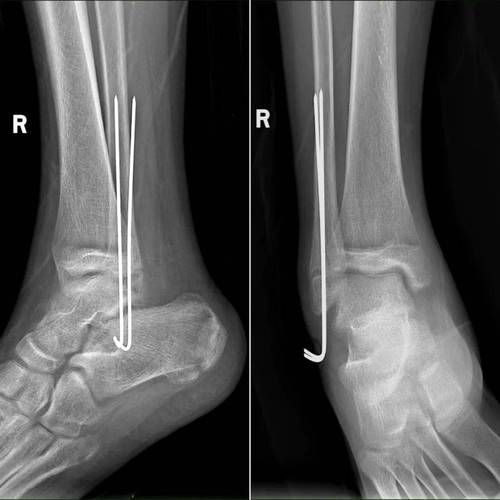

- 髓内钉适合长骨骨折

- 3D打印导板实现精准置钉